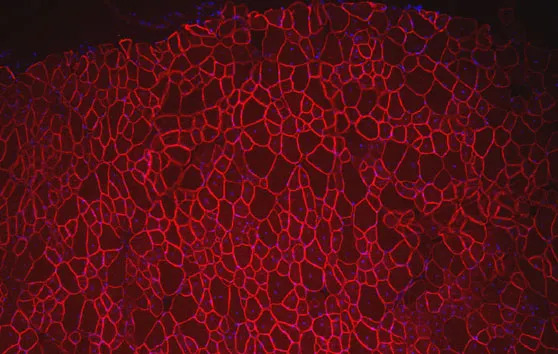

Généthon a étudié les interactions entre des protéines des myopathies des ceintures et d’autres protéines de l’organisme. Ces liens forment un réseau dense appelé Interactome.